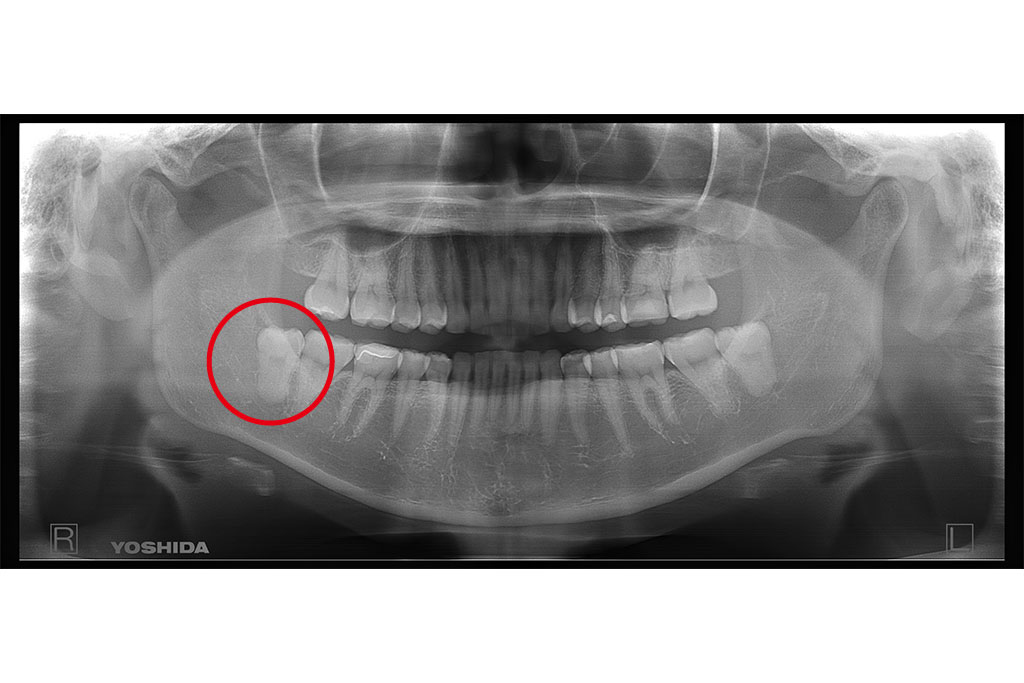

父のレントゲン写真と口腔内を見て、インプラントを入れる位置を一緒に決めて行きました。

右上は歯があるように見えて隣の歯につなげてある被せ物があるだけの状態です。

その右上は骨がないためサイナスリフトという処置を施した後にインプラントを入れる手術をしなければならないのですが、(サイナスリフトは骨を作るだけで6ヶ月待ちます。)

私は水口先生が開発したオステオプッシャーを用いて、骨がないところに骨を足す手術と並行してインプラントを入れる手術を施しました。

左側の入れ歯を入れていたと言っている場所には通常の方法でインプラント治療を、左上の奥歯2本は歯周病でグラグラだったため抜歯と同時にインプラントと治療を行いました。

左側のレントゲンがが最初の状態です。右側がインプラントを入れ、被せ物まで入れた状態のレントゲンです。